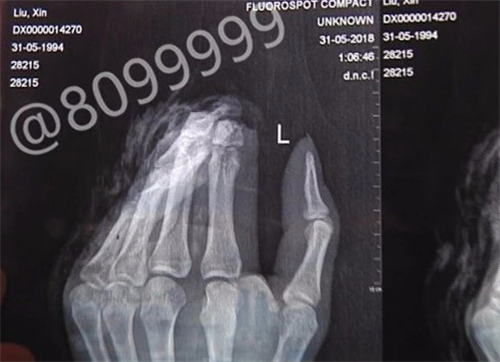

大板桥一小伙两根手指被斩断,在独自辗转求医途中不小心将断指遗失,多个部门和网友全力寻找,很遗憾的是,截至昨晚8点,小刘的两根断指还是没有找到,已错过24小时的最佳手术时间。

情况危急,小刘当即用粉白条纹相间的毛巾包起两根断指,前往云桥医院咨询能否治疗。得到否定答案后,他赶往官渡区人民医院。进行简单包扎后,医生让他赶紧去别的医院看看。9时20分左右,小刘打了一辆出租车,赶往延安医院。到达延安医院,医生让他拿出断指时,他才发现断指竟然不见了。因缺少断指,延安医院表示无法无法为小刘做再植手术,只能做残端处理,所以为他推荐到云南骨科医院进行修复重建手术。

抱着一线希望,小刘向云南骨科医院求助,并前往医院就诊。到达医院时,已是31日凌晨1点。云南骨科医院修复重建显微外科中心病区主任曹学新介绍,小刘两根断掉的手指占整根手指约二分之一。如果能在24小时内(昨晚8点前)找到,可通过手术接断指,手指存活可能性较大。“24小时不是绝对的,要看具体情况。如果手指相对完整,这个时间还能延长,但时间越长,成活率越低。”

经过一天的全城搜索,眼看断指找到的机会渺茫,加之时间过去太久,即使找到断指,再接且成活的几率也微乎其微,而小刘的伤口更需要尽快得到处理。考虑再三后,小刘于6月1日上午接受了残端修整手术,手术进行得很顺利,预计一周能出院。